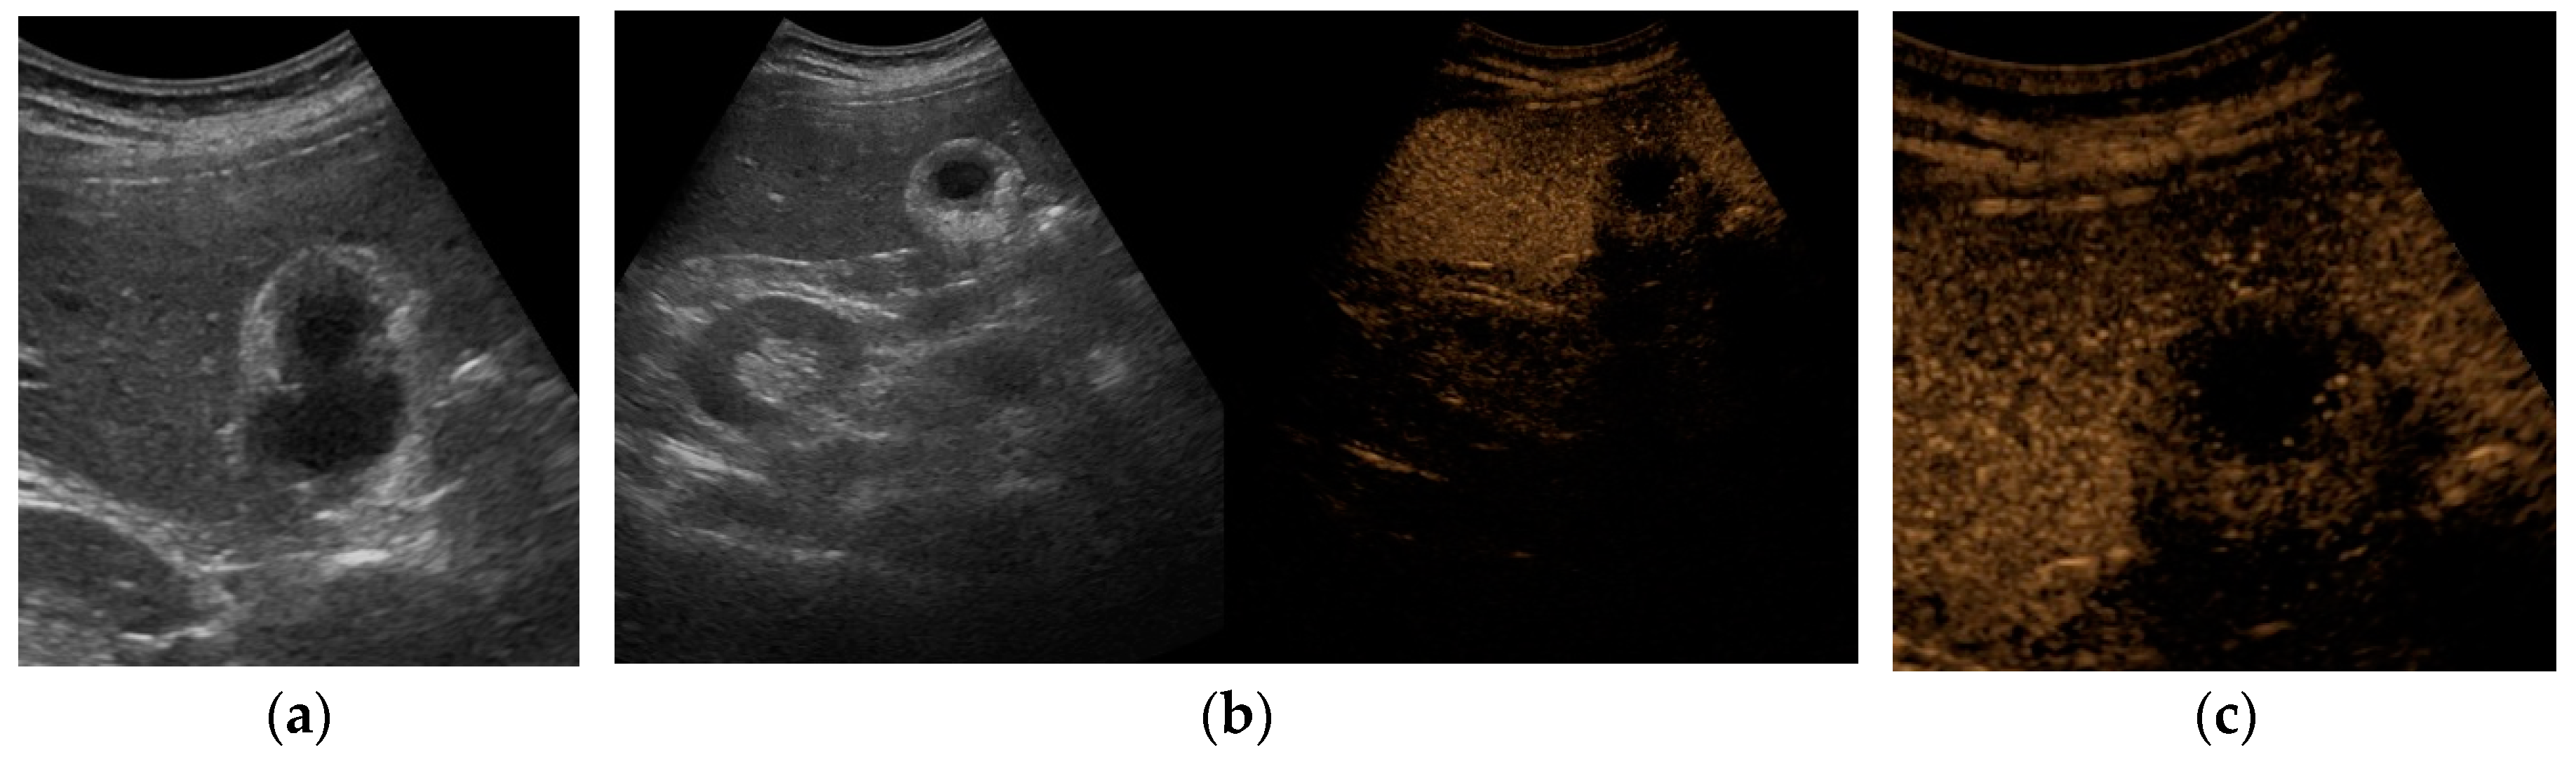

The US typical appearance of gallstones is an echogenic focus in the gallbladder lumen that casts a posterior acoustic shadow and changes position according to the variation of patient decubitus (Figure 1).[3] Stones smaller than 2 or 3 mm may be difficult to visualize, especially if isolated. Gallstones typically produce complete shadowing without reverberation because most of the ultrasound is absorbed by the stone. Rarely, reverberation artifacts may be seen posterior to calcified stones if they contain gas within fissures. [1]

Typically, biliary sludge is a slight sonographic finding,[1] which appears as non-shadowing echoes with an indefinite shape that tend to layer in the most declivous portion of the gallbladder. Biliary sludge forms a horizontal level that moves slowly, according to changes in patient’s decubitus (Figure 1). [1,2]

Rarely, aggregated sludge may appear as a static, variably echogenic, intraluminal mass, without acoustic shadows nor internal vascular signals, in close proximity with the gallbladder wall (“sludge ball”) or as a polypoid mass (“tumefactive sludge”). [2,3] A gallbladder completely filled with sludge may be isoechoic with the adjacent liver, leading to the so called “hepatization of the gallbladder”. [3] In this setting, it can be difficult to distinguish biliary sludge from polypoid lesions, if not from gallbladder carcinoma (GBC). [11,12]

CEUS can greatly improve the diagnostic confidence in the differential diagnosis between sludge and mass-forming lesions, especially when CD signals are not detectable. Indeed, sludge typically does not show any kind of enhancement at any contrast phase, due to the absence of vascularization, with an accuracy of 100%.[14,15,16,17,18,19,20]